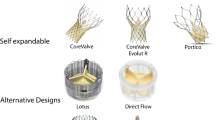

Transcatheter aortic valve implantation (TAVI) for symptomatic patients with severe aortic stenosis utilizes stent systems, in which a bioprosthetic valve is mounted. The procedure can be performed using a transfemoral, transcaval, transcarotid, transaxillary, transaortic, or transapical approach [6,7,8,9,10,11]. The stent/valve systems are anchored at the annulus and extend into the root or proximal ascending aorta. Since the initial successful human implantation in 2002, different generations of balloon-expandable or self-expandable valve prostheses have been implanted in several thousand patients with severe symptomatic aortic stenosis. The results in experienced centers are good, with high implantation success rate, significant hemodynamic and clinical improvements, and improved survival rates [11,12,13]. TAVI was associated with improved outcomes compared to medical therapy, and comparable outcomes to open-heart surgery [14]. See chapter on TAVI devices for more information.